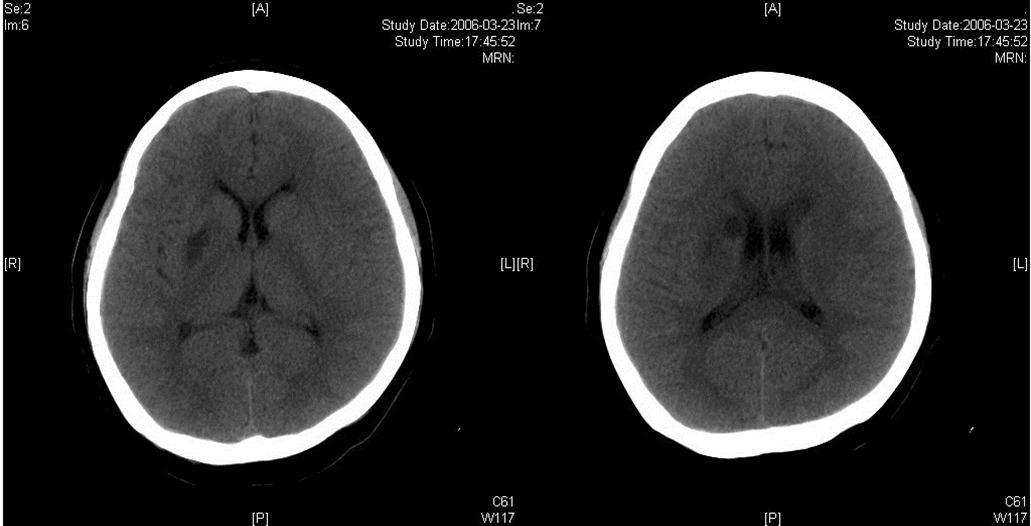

The same dose of aspirin, clopidogrel and subcutaneous LMWH was used after the operation. Two days after the stenting (Mar 23), three successive bouts of left limb weakness along with slight dizziness occurred, lasting about 10 minutes with intervals of 30 minutes. There were no abnormal signs between the first and second attacks. Babinski sign was noted during the second attack and persisted in the left between the second and third attacks with normal muscle strength, but she felt weakness. Blood pressure was 140/70 mmHg. After the third attack, her tongue deviated slightly to the left side. There was slight decrease in muscle strength and Babinski sign was positive in the left. Emergent CT displayed two low density lesions with clear edge and homogeneous density in the right basal ganglia (Figure 3). Aspirin 300mg was given emergently. Compared with the Transcranial Doppler (TCD) test before the operation (March 3), emergent TCD showed the blood flow velocity increased significantly in both anterior cerebral artery (ACA), especially in right ACA (Table 1). She got partial recovery after being given volume expansion treatment with low molecular dextran. Then she was given anticoagulant treatment with intravenous unfractionated heparin (UFH) (500 U/h). LMWH was stopped. On the next day, her muscle strength recovered to normal, but pathological sign persisted. Anticoagulation therapy was continued along with dual antiplatelet therapy. On Mar 25, limb weakness appeared again, muscle strength was Ⅳ grade in the left, both Babinski sign and Chaddock sign were positive. Volume expansion with low molecular dextran was ineffective, and the dose of UFH was increased to750 U/h. Two days later, muscle strength and plantar reflex recovered to normal. On Mar 27, CT scan revealed that the lesion did not change compared with the previous scan, and there was no new lesion. Dose of UFH was reduced to 500H/h. During treatment, blood coagulation test was performed for several times, PT was stabled at 14.1~15.5 sec, APTT at 32.7~43.1 sec, INR at 66.6%~78.8%, activity of antithrombin Ⅲ (AT Ⅲ) at 70.4%~97.2%, and fibrinogen at 3.93~4.68 g/L. UFH was replaced by LMWH on Mar 31. CTA (Apr 3) displayed the stent was in M1 segment of right MCA, its proximal lumen was attenuated compared with the left MCA, with slightly compromised distal blood flow (Figure 4).

Figure 3.Two infarcts displayed in CT images

Two infarcts displayed in CT images

The right MCA stenosis, which led to the transient ischemic attack (TIA) symptoms, was definitely diagnosed. Angioplasty and stenting was conducted after full preparation of dual anti-platelet therapy. Immediately before the operation, LMWH was used in combination and was continued after operation. Her condition was stable in the first two days after operation. Then crescendo TIA recurred and led to motor impairment. Two lesions were shown in the emergent CT images. One was near the anterior horn of the right lateral ventricle, by which it was difficult to explain the symptoms and physical signs. The other was in basal ganglia, and was related to the symptoms and signs. The signal in this region had been slightly higher than the counterpart in the left in the source image of MRA before operation. Hence the lesion in basal ganglia was thought to result from hemodynamic impairment in distal parts of stenotic MCA. Both lesions had clear boundaries, which indicated that the infarction in the area supplied by deep branch of MCA occurred before the TIA attacks. The crescendo TIA worsened gradually, but got partial recovery after volume expansion treatment initially. TCD test showed the blood flow velocity increased in both ACA, especially in the right, while that in the right MCA did not significantly increase. This indicated that some collateral circulation had formed, to counteract hypoperfusion caused by progressive stenosis in the right MCA. Based on these, we deduced that there was IST which did not completely block the right MCA. The symptoms and physical signs appeared again when there was failure of collateral compensation. Because there were new lesions on CT scan and the patient had been treated with dual anti-platelet treatment and anticoagulation, thrombolytic therapy could not be given. So we gave unfractionated heparin (UFH). The symptoms and physical signs disappeared on the next day. But two days later during the same treatment, the symptoms and signs recurred, volume expansion was ineffective, this indicated that initial recovery of symptoms was due to compensatory collateral circulation, and anticoagulation therapy with UFH may also play a role. But this could not prevent thrombosis from progressing, so we increased the dose of anticoagulation drugs, the symptoms and signs disappeared eventually. CTA (Apr 3) and repeated TCD (Apr 17) confirmed our reasoning with attenuated proximal lumen of right MCA and increased blood flow velocities of the right MCA and ICA.